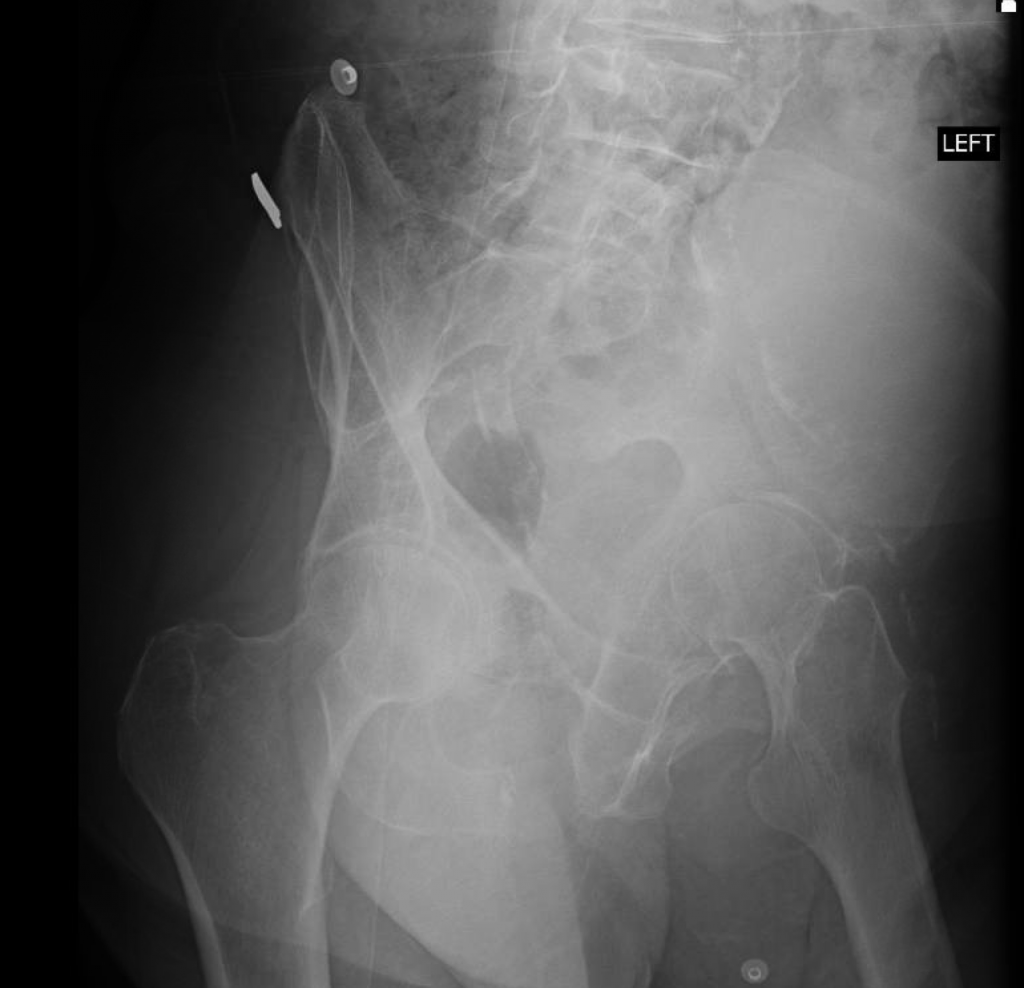

The patient underwent simultaneous acetabular ORIF and complex THA reconstruction by Dr. Darwin Chen and Dr. David Forsh (Chief of Orthopaedic Trauma). A Kocher-Langenbeck approach was used for exposure. The anterior and posterior columns were secured together using a single posterior-to-anterior screw just superior to the acetabulum. An acetabular shell was implanted with excellent inherent stability, followed by screw fixation into the superior dome as well as inferiorly into the ischium.

After a period of limited weight bearing, the patient was able to return to full function without deficits.